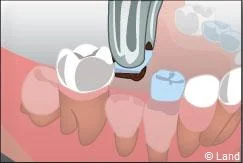

Lorsque des dents de lait ont été extraites trop tôt parce qu’elles étaient cariées, les dents de part et d’autre peuvent migrer et combler l’espace, bloquant ainsi l’éruption des dents définitives. Il est alors nécessaire de maintenir cet espace avec un appareillage spécifique appelé « mainteneur d’espace » jusqu’à l’évolution des dents définitives.

De plus, il est opportun de corriger très tôt certaines malpositions. Les appareils généralement utilisés sont amovibles avec une armature en résine, mais peuvent aussi être fixes à l’aide de bagues sur les premières molaires définitives.. Suivant leurs conceptions et la manière dont ils sont portés, ils auront une action sur la position des dents mais aussi sur la croissance.